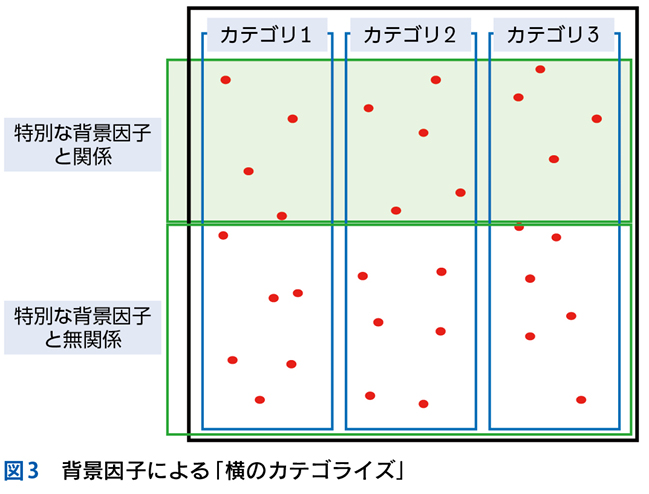

▶ 症例によっては,ここまで述べたような条件を満たす問題を複数定義できることがある。この場合は,それぞれの問題が描くフレームが重なり合うところに診断があると考えるとよい(図3)。